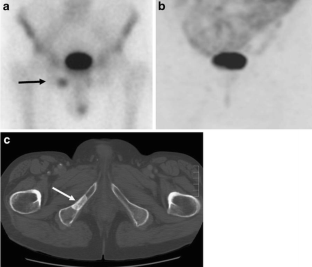

Fig. 2

Fig. 3

Fig. 4

Fig. 5